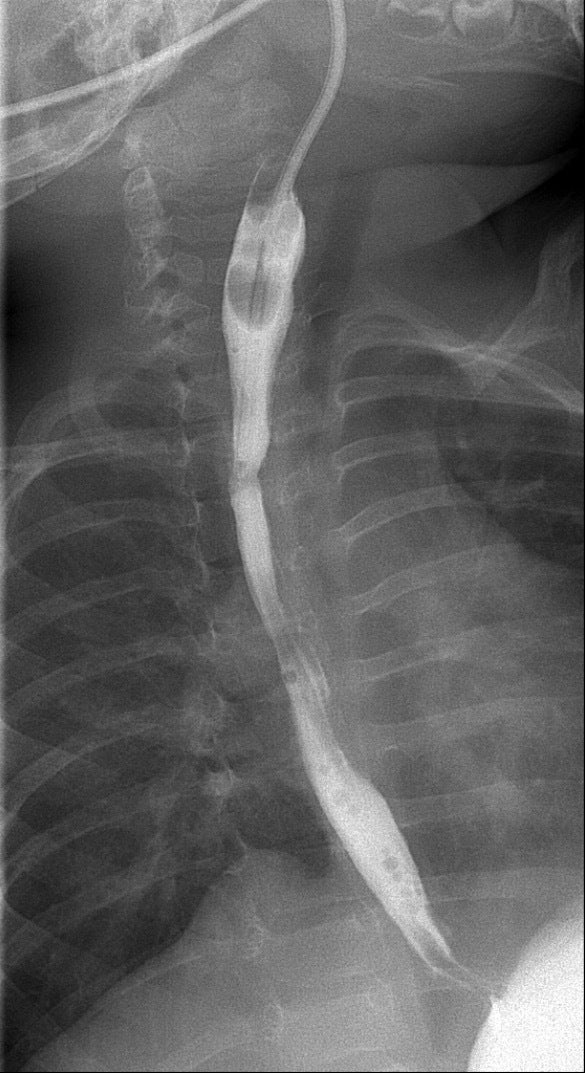

Een andere complicatie die kan optreden, is een vernauwing van de slokdarm. Dit is meestal ter hoogte van de nieuwe verbinding als gevolg van littekenweefsel. Hierdoor kan er weinig voeding langs en kan uw kind slechter gaan drinken, gaan spugen, slijm opgeven of minder lucht krijgen. De vernauwing kunnen we in beeld brengen met röntgen contrastvloeistof, zie figuur 3. Een vernauwing kunnen we onder narcose oprekken. Dit is soms meerdere keren en op verschillende momenten in de toekomst nodig. Voor het oprekken gebruiken we meestal speciale ballonnen. Bij terugkerende vernauwingen kunnen we de ballon in de slokdarm achterlaten. De ballon kan dan in de thuissituatie meerdere keren per dag worden opgeblazen, om zo een terugkeer van de vernauwing te voorkomen.